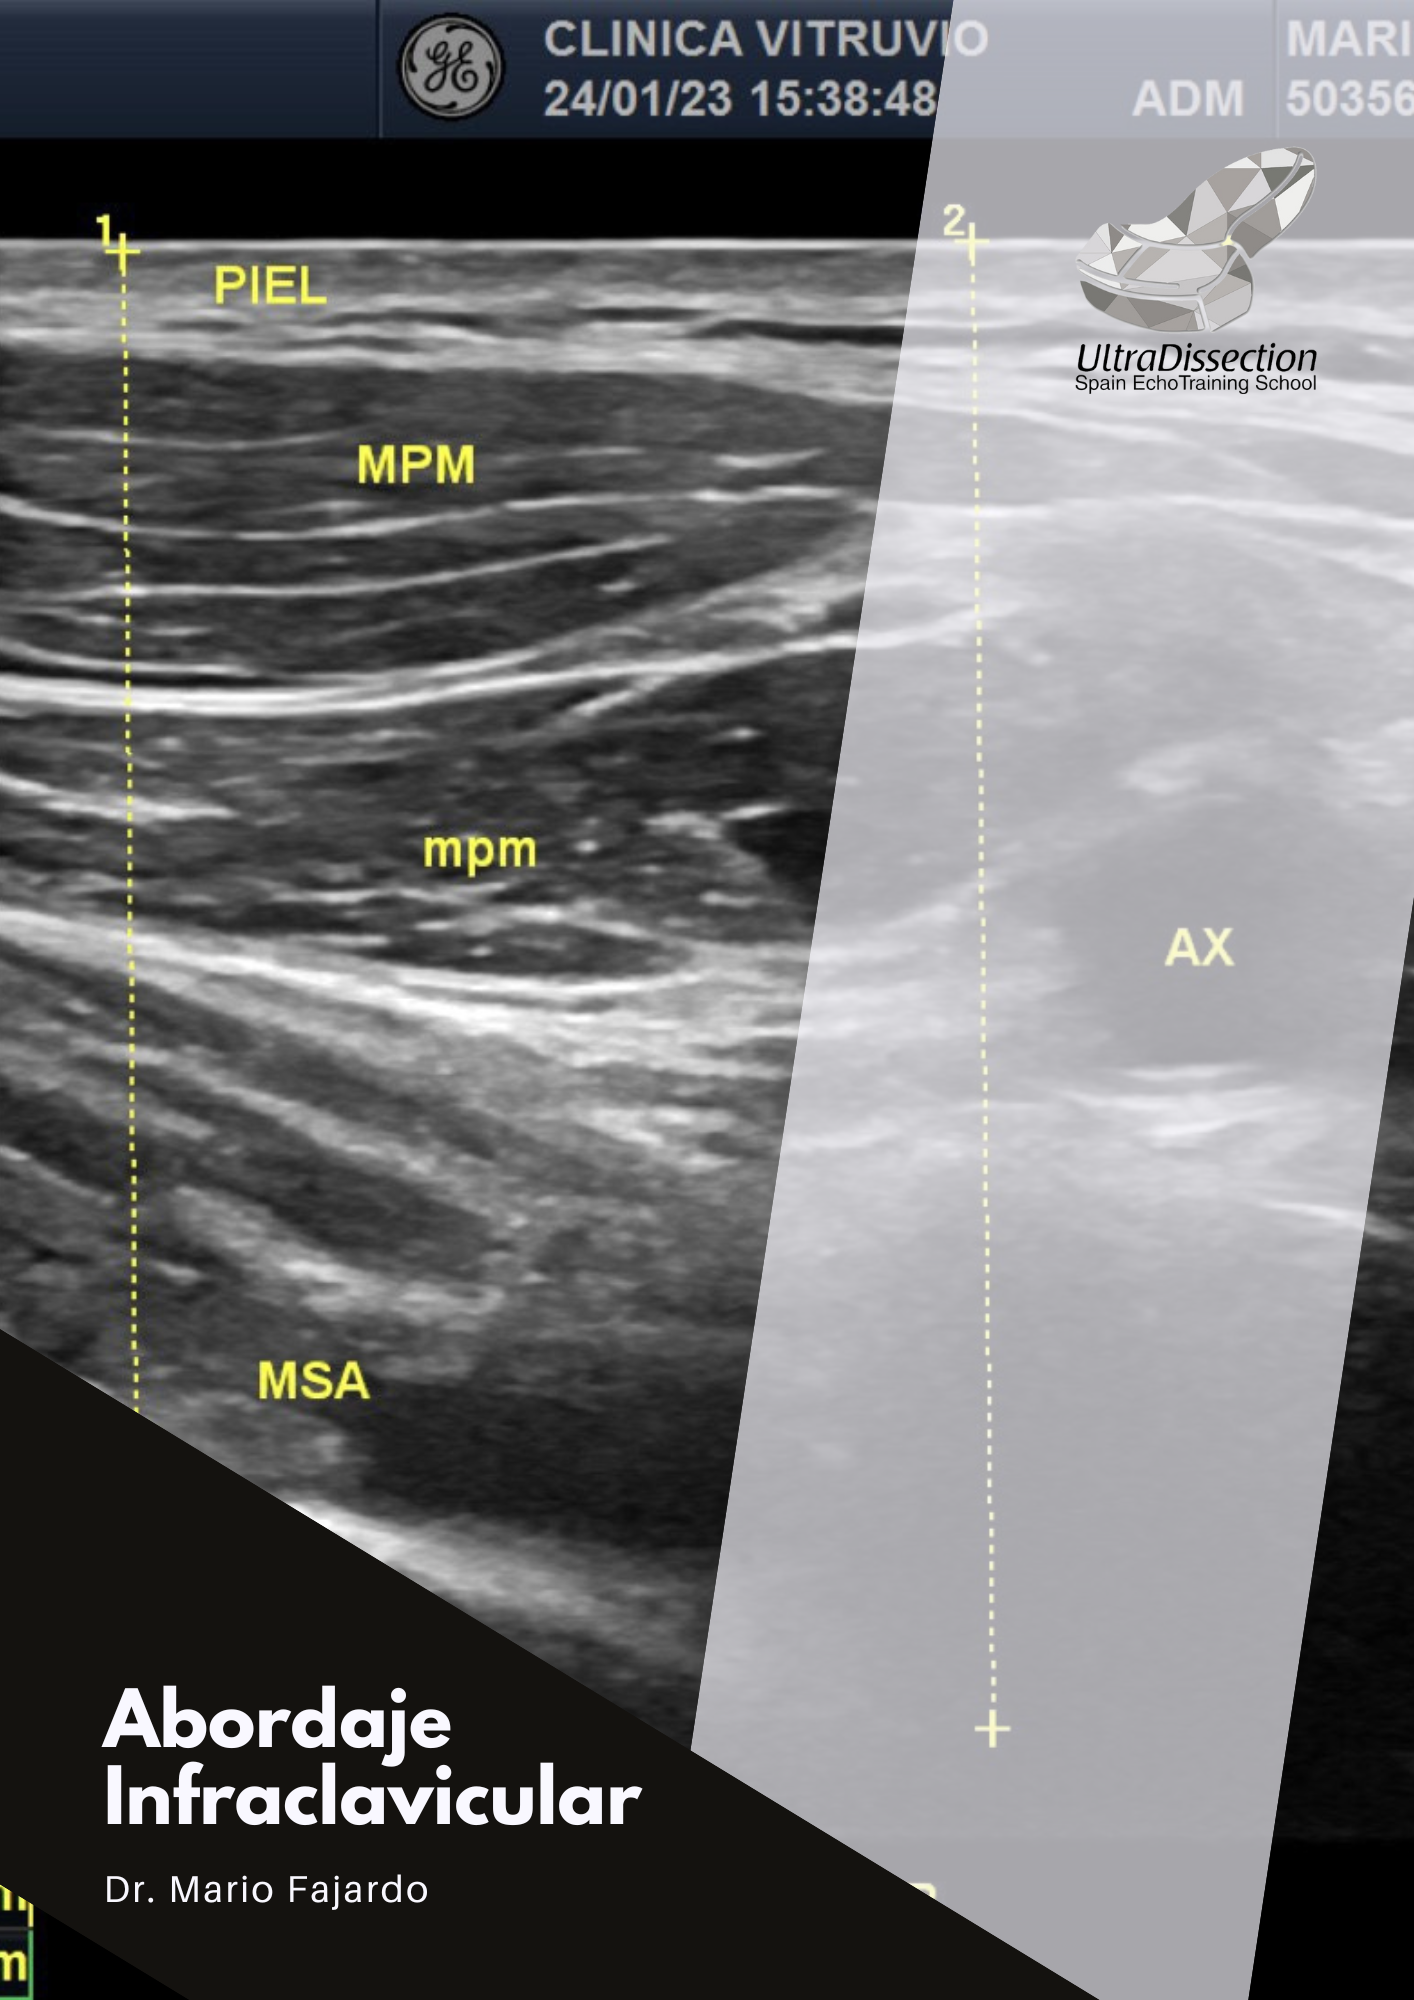

Este recurso visual especializado del UltraDissection Group, guiado por el Dr. Mario Fajardo, te lleva a través del abordaje infraclavicular con una perspectiva anatómica precisa y orientada a la práctica clÃnica. Ideal para quienes buscan dominar este acceso esencial en anestesia regional y procedimientos intervencionistas.

Trayectoria del plexo braquial a nivel infraclavicular

Relación con estructuras como arteria y vena axilar

Orientación por ultrasonido y planos anatómicos

Imágenes reales con rotulación detallada y explicaciones clave

This advanced visual resource from UltraDissection Group, led by Dr. Mario Fajardo, walks you through the infraclavicular approach with precise anatomical focus and real clinical context. A must-have for mastering this essential access in regional anesthesia and interventional procedures.

Course of the brachial plexus at the infraclavicular level

Relationship to axillary artery and vein

Ultrasound guidance and fascial plane orientation

Real dissection images with detailed labels and key explanations